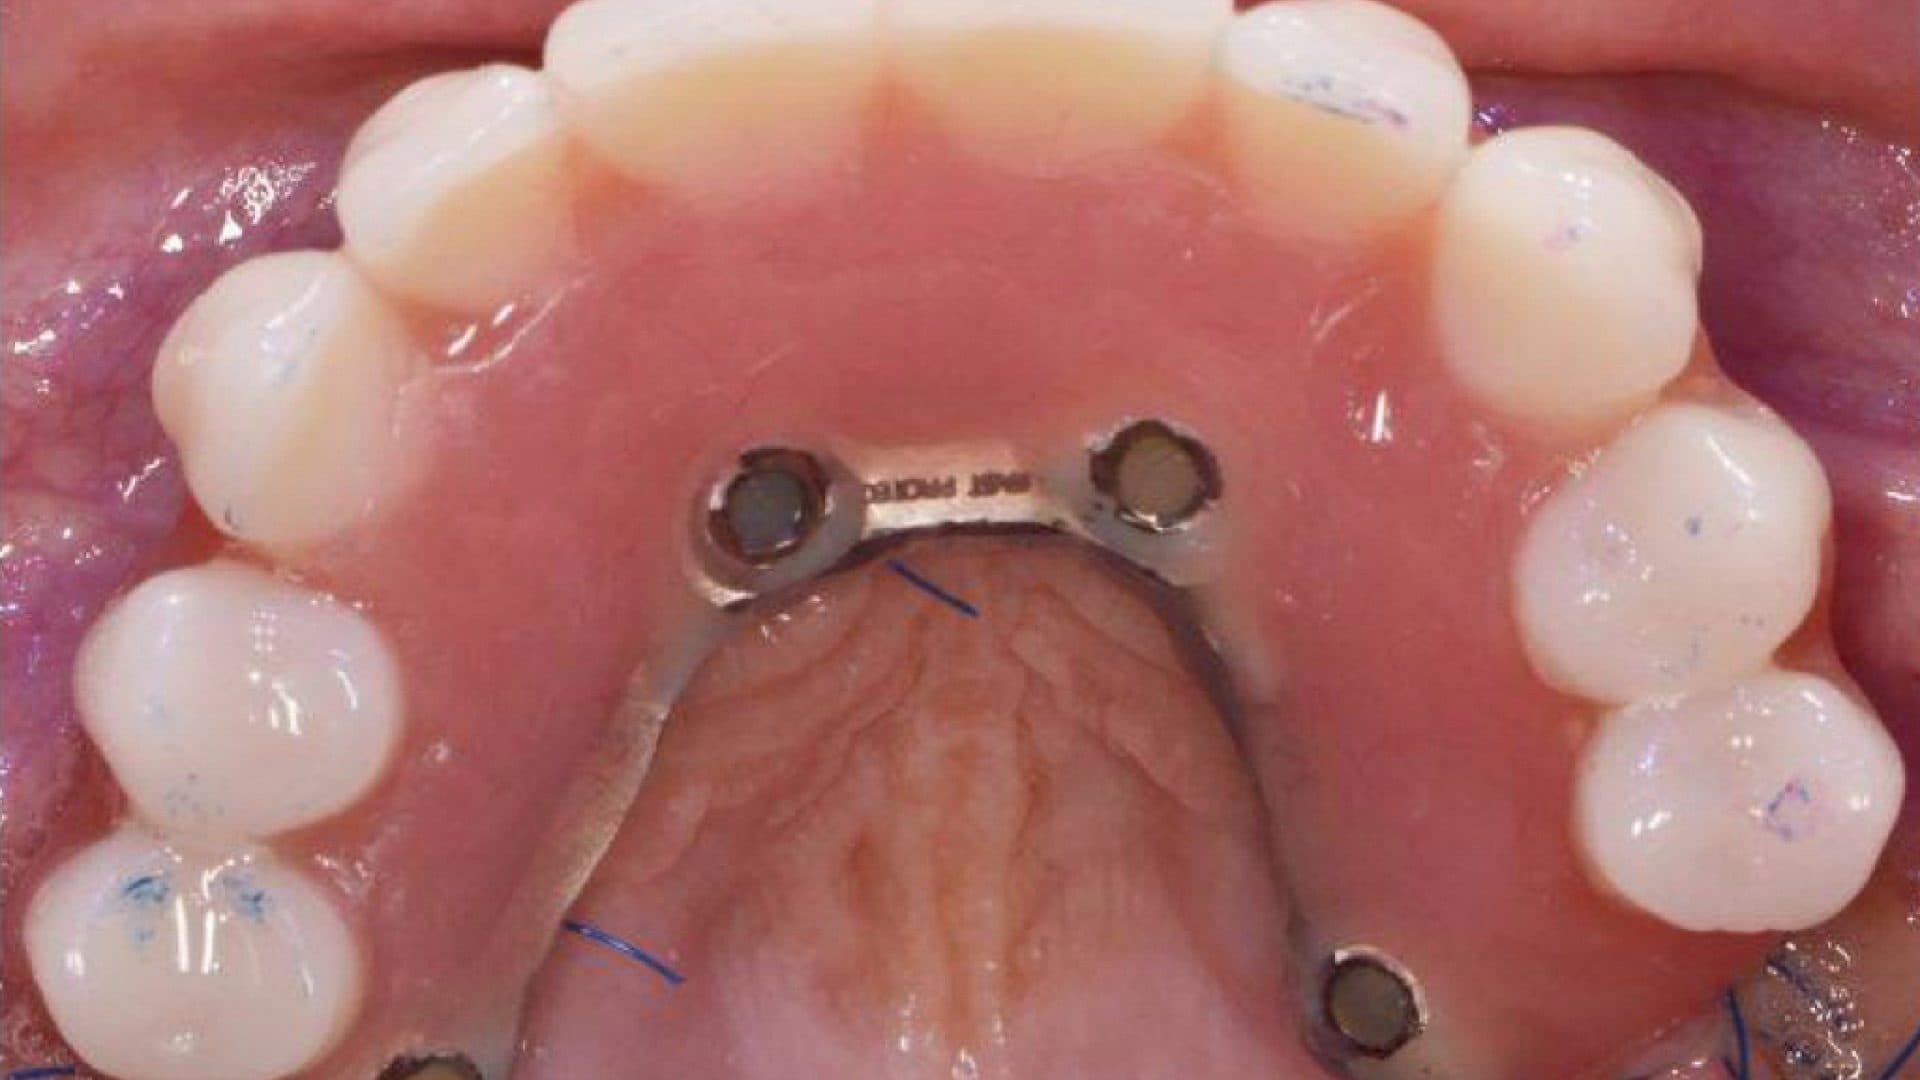

Examples Of Poor Standards

iii. Alignment on x-rays: there should be even spread, rigid connection between the implants, good bone levels, and the height of the prosthesis should be at least as tall as the shortest fixture (See pictures).

Ideal Situation